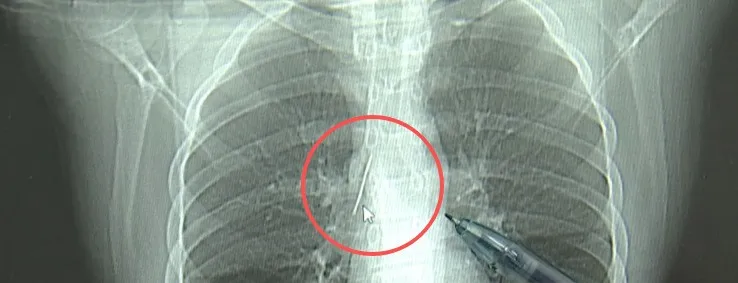

●17岁小伙胸腔内有根5cm缝衣针,父母回忆或是1岁时扎入

近日,安徽17岁小伙小陆参加征兵体检,胸片结果显示胸腔内有一根针,位置十分凶险。经小陆父母反复回忆,这根针或是在小陆1岁多时扎入体内的。近日,医生成功取出这根长达5cm左右的针。【详讯】